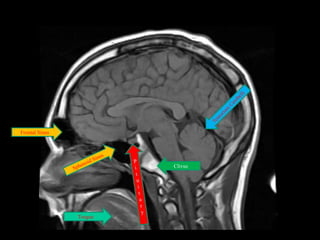

Frontal Sinus

Clivus

Tongue

Superior Saggital Sinus

Frontal Sinus Clivus Tongue